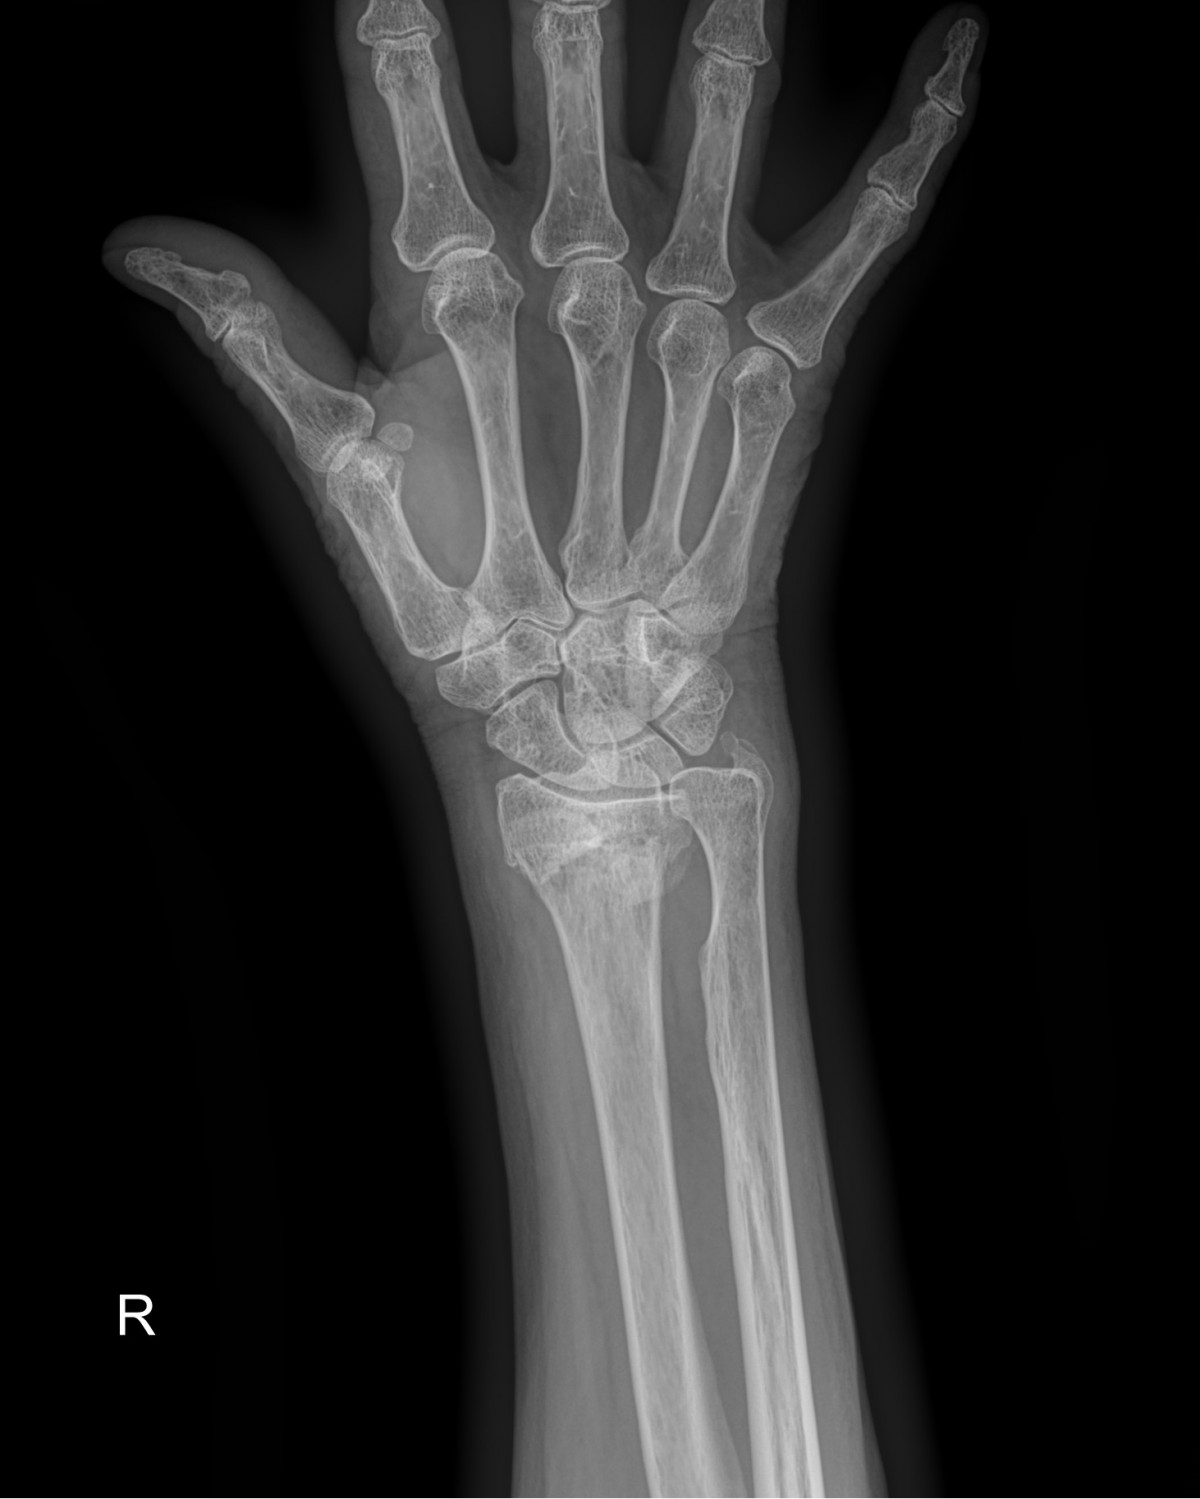

정지영원장님 손목 골절 수술 강복O 환자

dae765e4d9ac96aee867c9d6292d8784_1758008041_3783.jpg